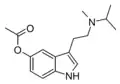

| DiPT | artificial | H | CH(CH3)2 | CH(CH3)2 | N,N-diisopropyltryptamine | 14780-24-6 |